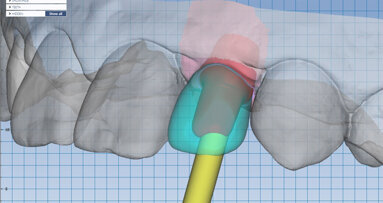

Obr. 1: CAD/CAM chirurgické šablony zcela omezují sklon vrtáku a hloubku preparace a jsou navrženy na základě dat týkajících se konkrétního pacienta z CBCT skenu a z intraorální kamery zpracovaných softwarem pro plánování implantátů

Obr. 2: Zkombinování CBCT a dat z intraorálních skenů usnadňuje podrobné, přesné předoperační plánování